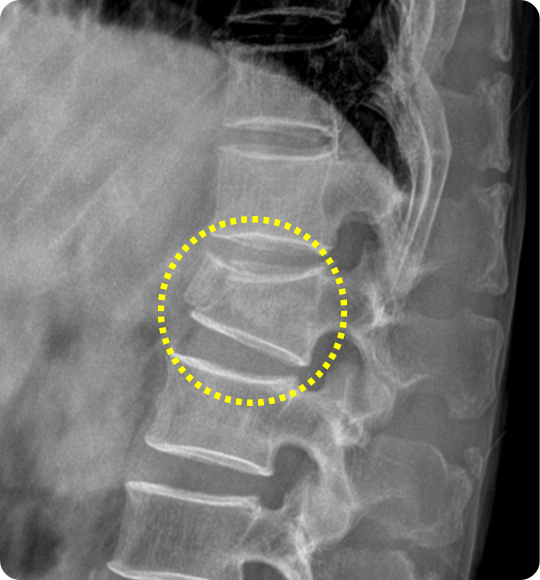

척추 압박골절의 양상과 진행 정도에 따라 척추체 성형술과, 주저앉은 척추

높이를 일부 회복시키는 풍선 척추성형술이 적용될 수 있습니다.

척추체 성형술 후